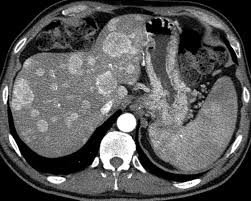

- Diaqnozu dəqiqləşdirmək üçün Qc venaları yoxlanılmalıdır. Bunun üçün dopler USM, KT-angioqrafiya, MRT-angioqrafiyalar və ya kontrastlı venoqrafiya edilir.

- Görüntüləmədə Qc venalarının trombotik tutulması diaqnozu dəqiqləşdirən əlamətdir.

PVT diaqnozunu dəqiqləşdirmək üçün portoqrafiya aparılır – Doppler USM, KT və ya MRT angioqrafiya.

- Kontrastlı müayinələrdə damarda tromb və ya kavernoz transformasiya

Qaraciyər venalarının görünməməsi, kontrastlaşmaması və ya trombla tıxanması.

- portoqrafiyada vena mənfəzində trombun görünməsi;

- venanın distalında genişlənmə və kavernoz transformasiyanın görünməsi;